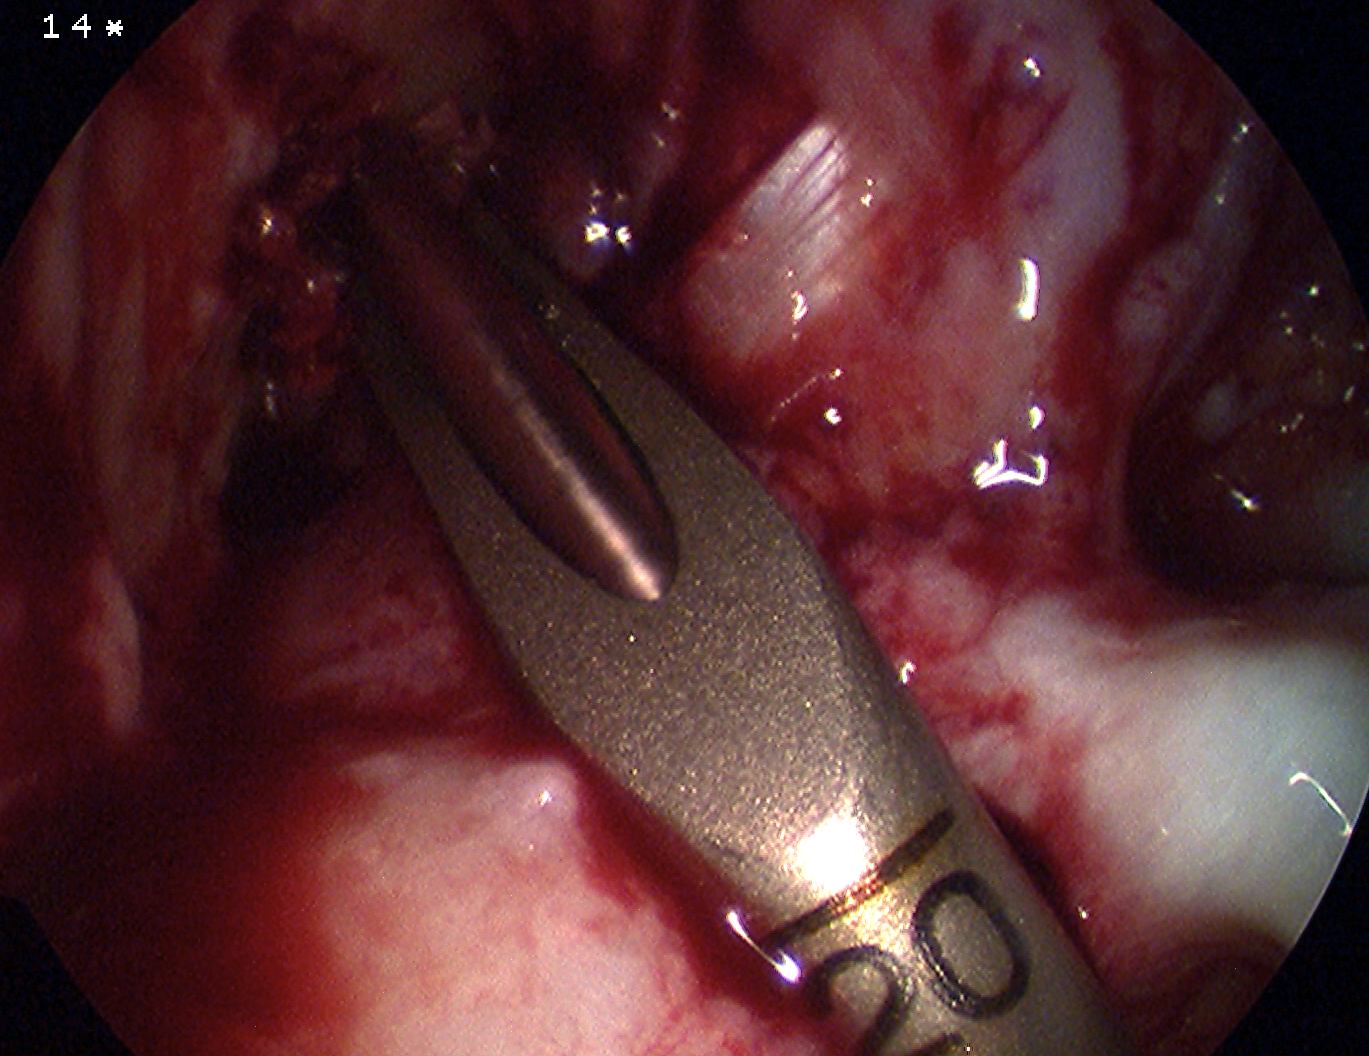

Pass graft

- ensure bone plug passes easily into tibial tunnel

- pull up gently on sutures and advance the bone plug into knee

- use grasper to align the bone plug with the femoral tunnel

- then pull on sutures and advance the plug into the tennel

- pull femoral bone plug deep into tunnel and tension